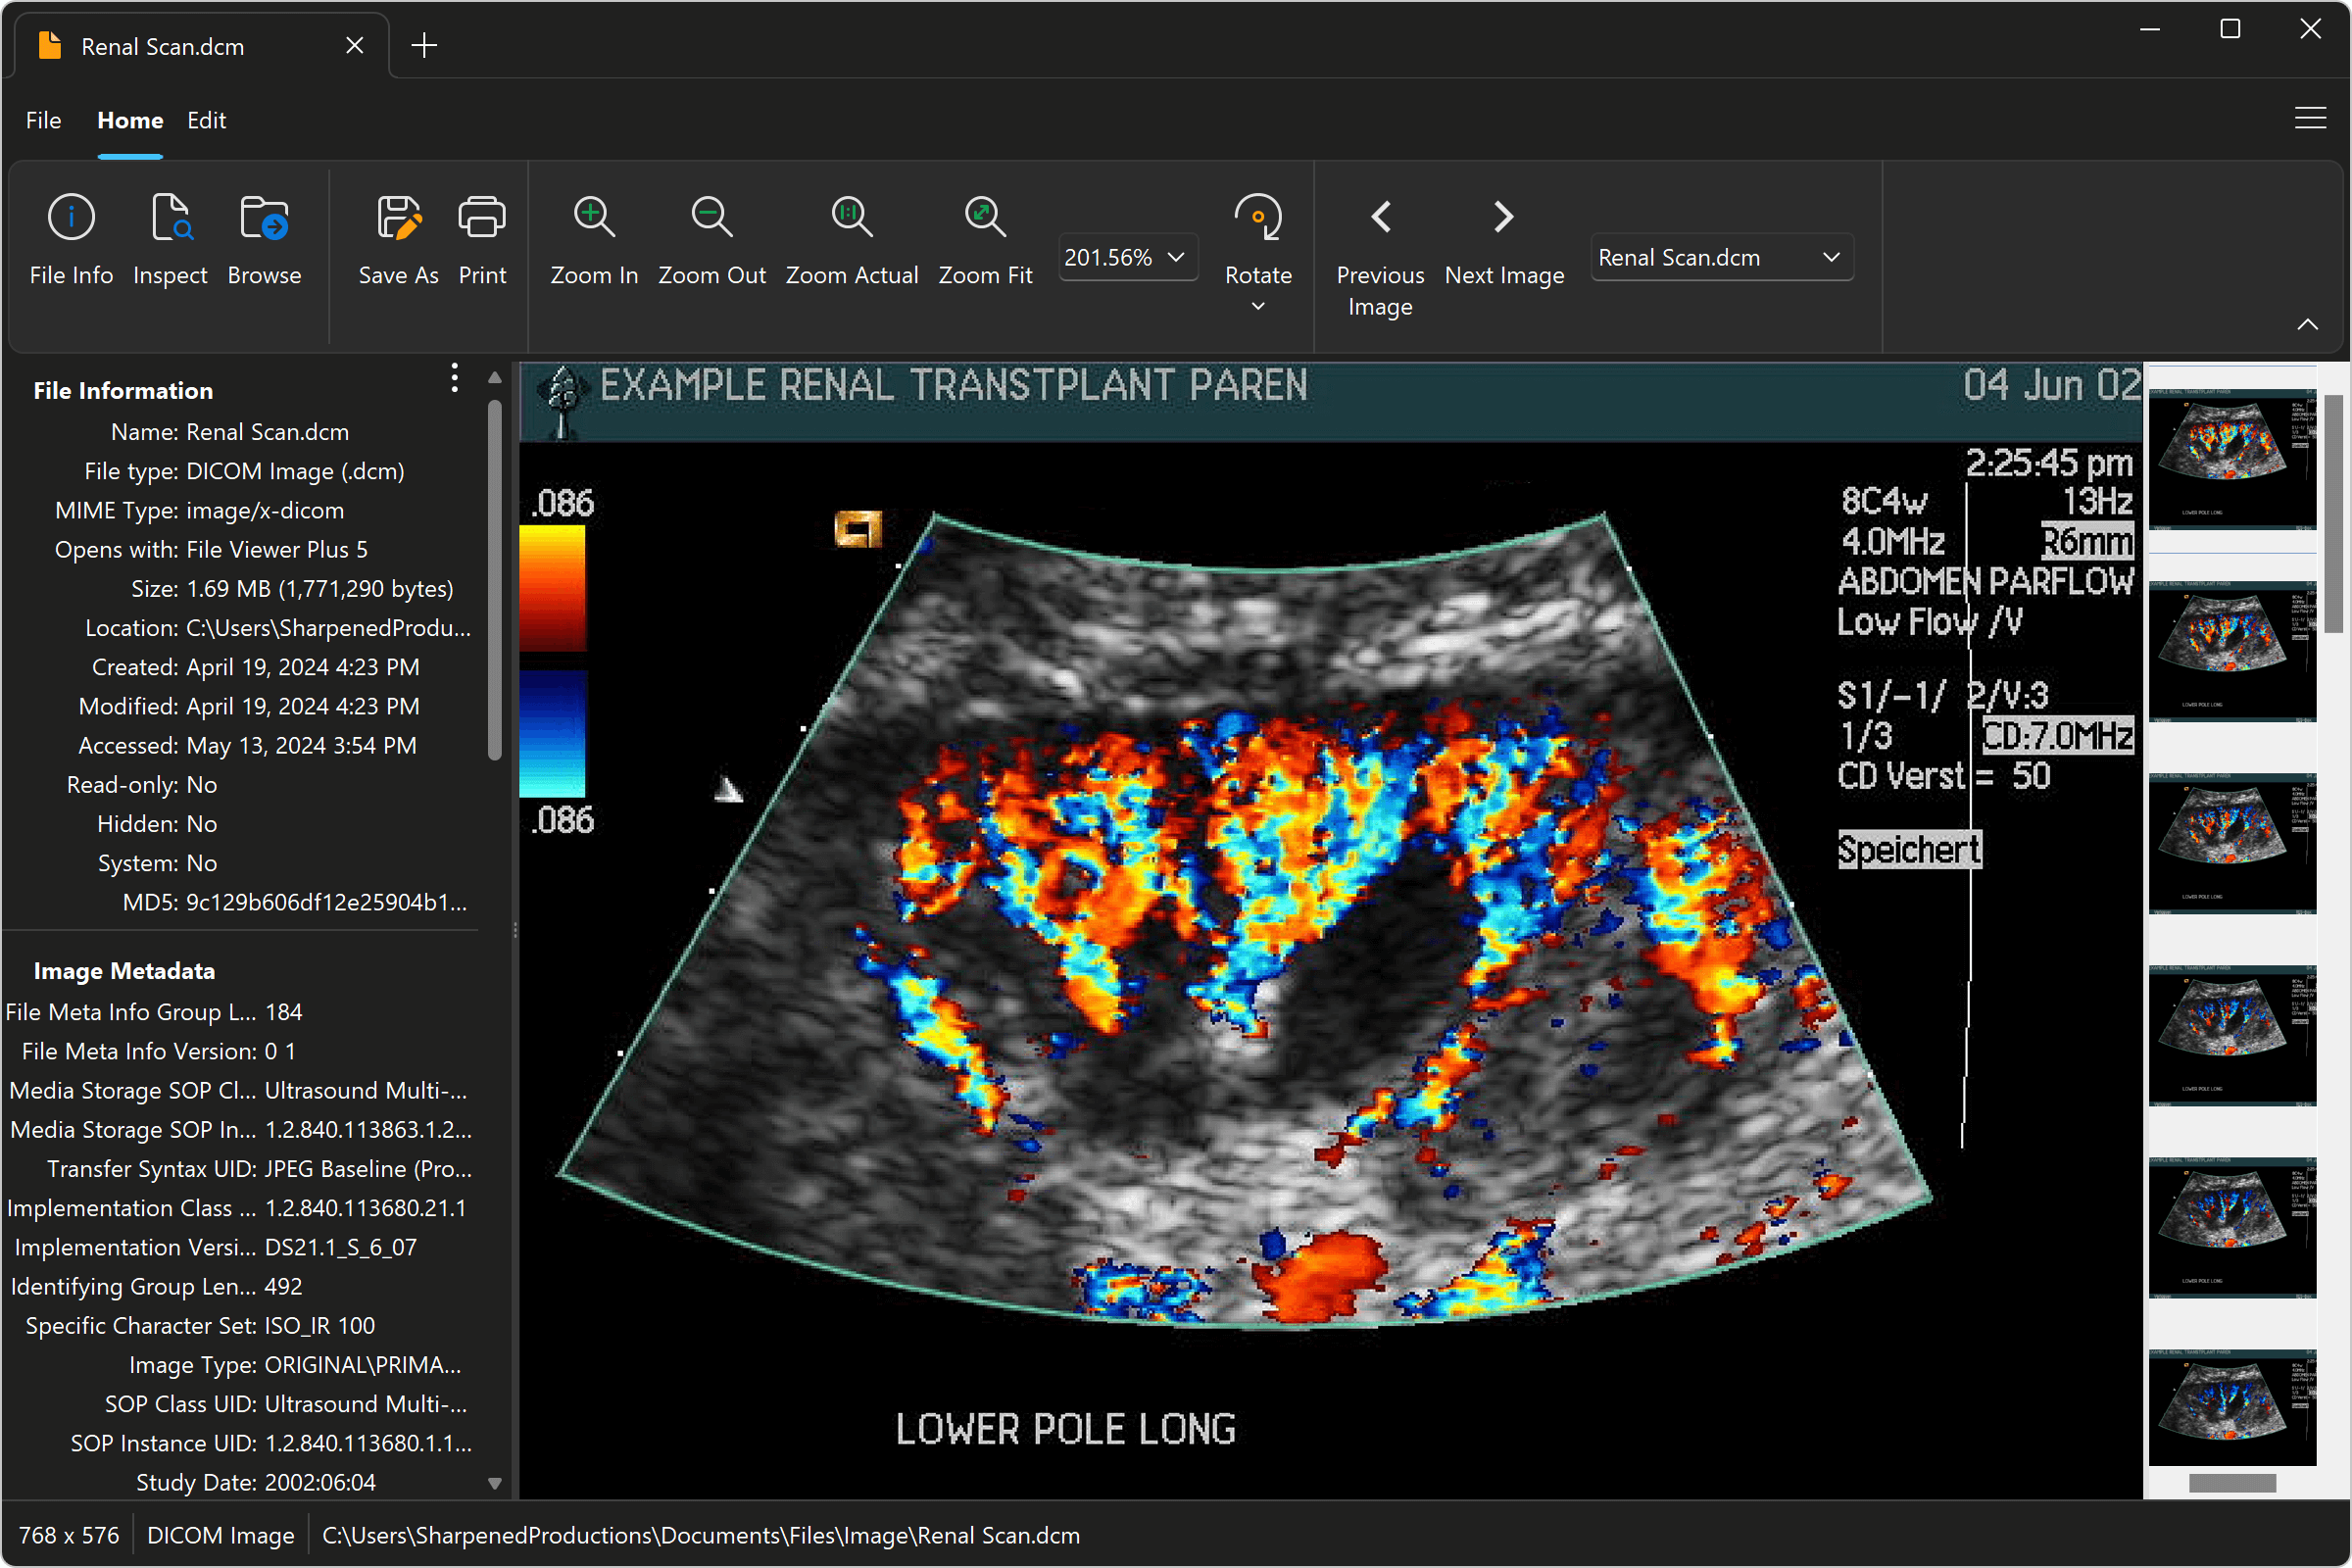

Le format DICOM (Digital Imaging and Communications in Medicine) est la norme internationale pour le stockage et l'échange d'images médicales. Un fichier DCM, extension du format DICOM, contient des informations telles que des radiographies, des scanners, des IRM et autres données d'imagerie médicale. Savoir comment afficher ces fichiers est donc primordial pour un diagnostic précis et un suivi médical adéquat.

Plusieurs solutions existent pour afficher un fichier DCM. Des logiciels gratuits comme MicroDicom ou Horos sont disponibles, offrant des fonctionnalités basiques pour la visualisation des images. Des solutions payantes plus avancées, telles qu'Osirix MD, proposent des outils d'analyse et de manipulation d'images plus poussés. Le choix du logiciel dépend des besoins de l'utilisateur.

Les avantages d'utiliser un visualiseur DICOM dédié sont nombreux. Premièrement, la qualité d'affichage est optimisée pour une interprétation précise des images médicales. Deuxièmement, ces logiciels offrent des outils de mesure, de zoom et de manipulation d'images, facilitant l'analyse. Troisièmement, ils permettent souvent l'intégration avec d'autres systèmes d'information médicale, simplifiant la gestion des données patients.

Pour ouvrir un fichier DCM, il suffit généralement de double-cliquer sur le fichier. Si aucun logiciel compatible n'est installé, Windows vous proposera de rechercher une application appropriée. Vous pouvez aussi ouvrir le logiciel directement puis importer le fichier DCM via l'interface du programme.